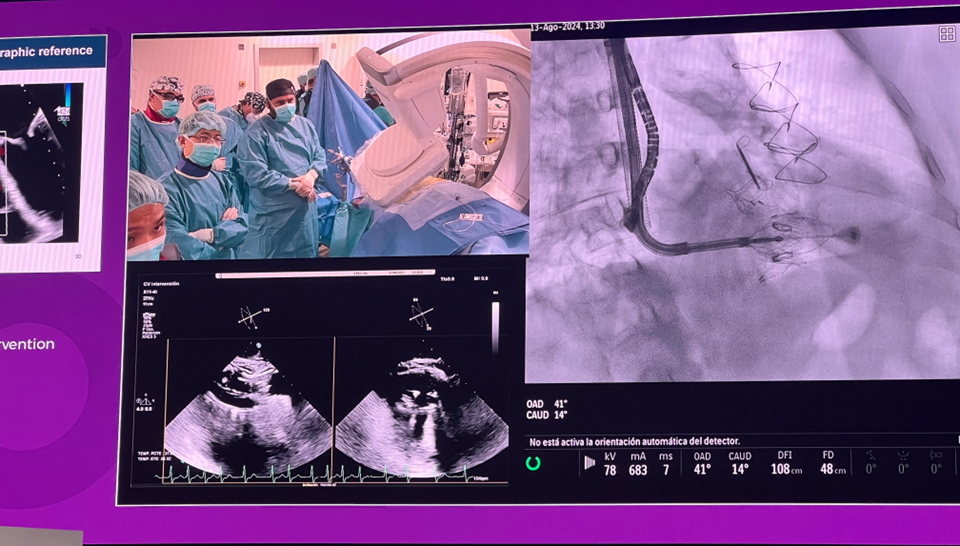

隨后由來(lái)自西班牙維哥-阿爾瓦羅昆奎羅醫(yī)院(Hospital Álvaro Cunqueiro, Vigo, Spain)的 Rodrigo Estevez-Loureiro 教授在大會(huì)主會(huì)場(chǎng)的經(jīng)導(dǎo)管介入瓣膜新技術(shù)環(huán)節(jié),帶來(lái)了一例 LuX-Valve Plus 手術(shù)錄播,對(duì)手術(shù)植入的步驟和關(guān)鍵要點(diǎn)進(jìn)行了詳細(xì)深入的介紹。同時(shí),臺(tái)上的多位討論嘉賓也結(jié)合他們的 LuX-Valve Plus 手術(shù)經(jīng)驗(yàn)進(jìn)行了深入的探討。來(lái)自香港瑪麗皇后醫(yī)院(Queen Mary Hospital, Hong Kong, China)的 Simon Lam 教授分享了 LuX-Valve Plus 在術(shù)前有起搏導(dǎo)線病人中的植入經(jīng)驗(yàn),來(lái)自巴西圣保羅(Rede D'Or São Luiz, São Paulo, Brazil)的 Vinicius Esteves 教授補(bǔ)充了 LuX-Valve Plus 獨(dú)特的非徑向支撐力設(shè)計(jì),能夠?qū)崿F(xiàn)非常低的術(shù)后起搏器植入率,來(lái)自法國(guó)波爾多大學(xué)醫(yī)院(CHU de Bordeaux, Bordeaux, France)的 Lionel Leroux 教授則分享了其在LuX-Valve Plus歐洲臨床試驗(yàn)過(guò)程中,對(duì)于大尺寸瓣環(huán)植入的優(yōu)異結(jié)果。